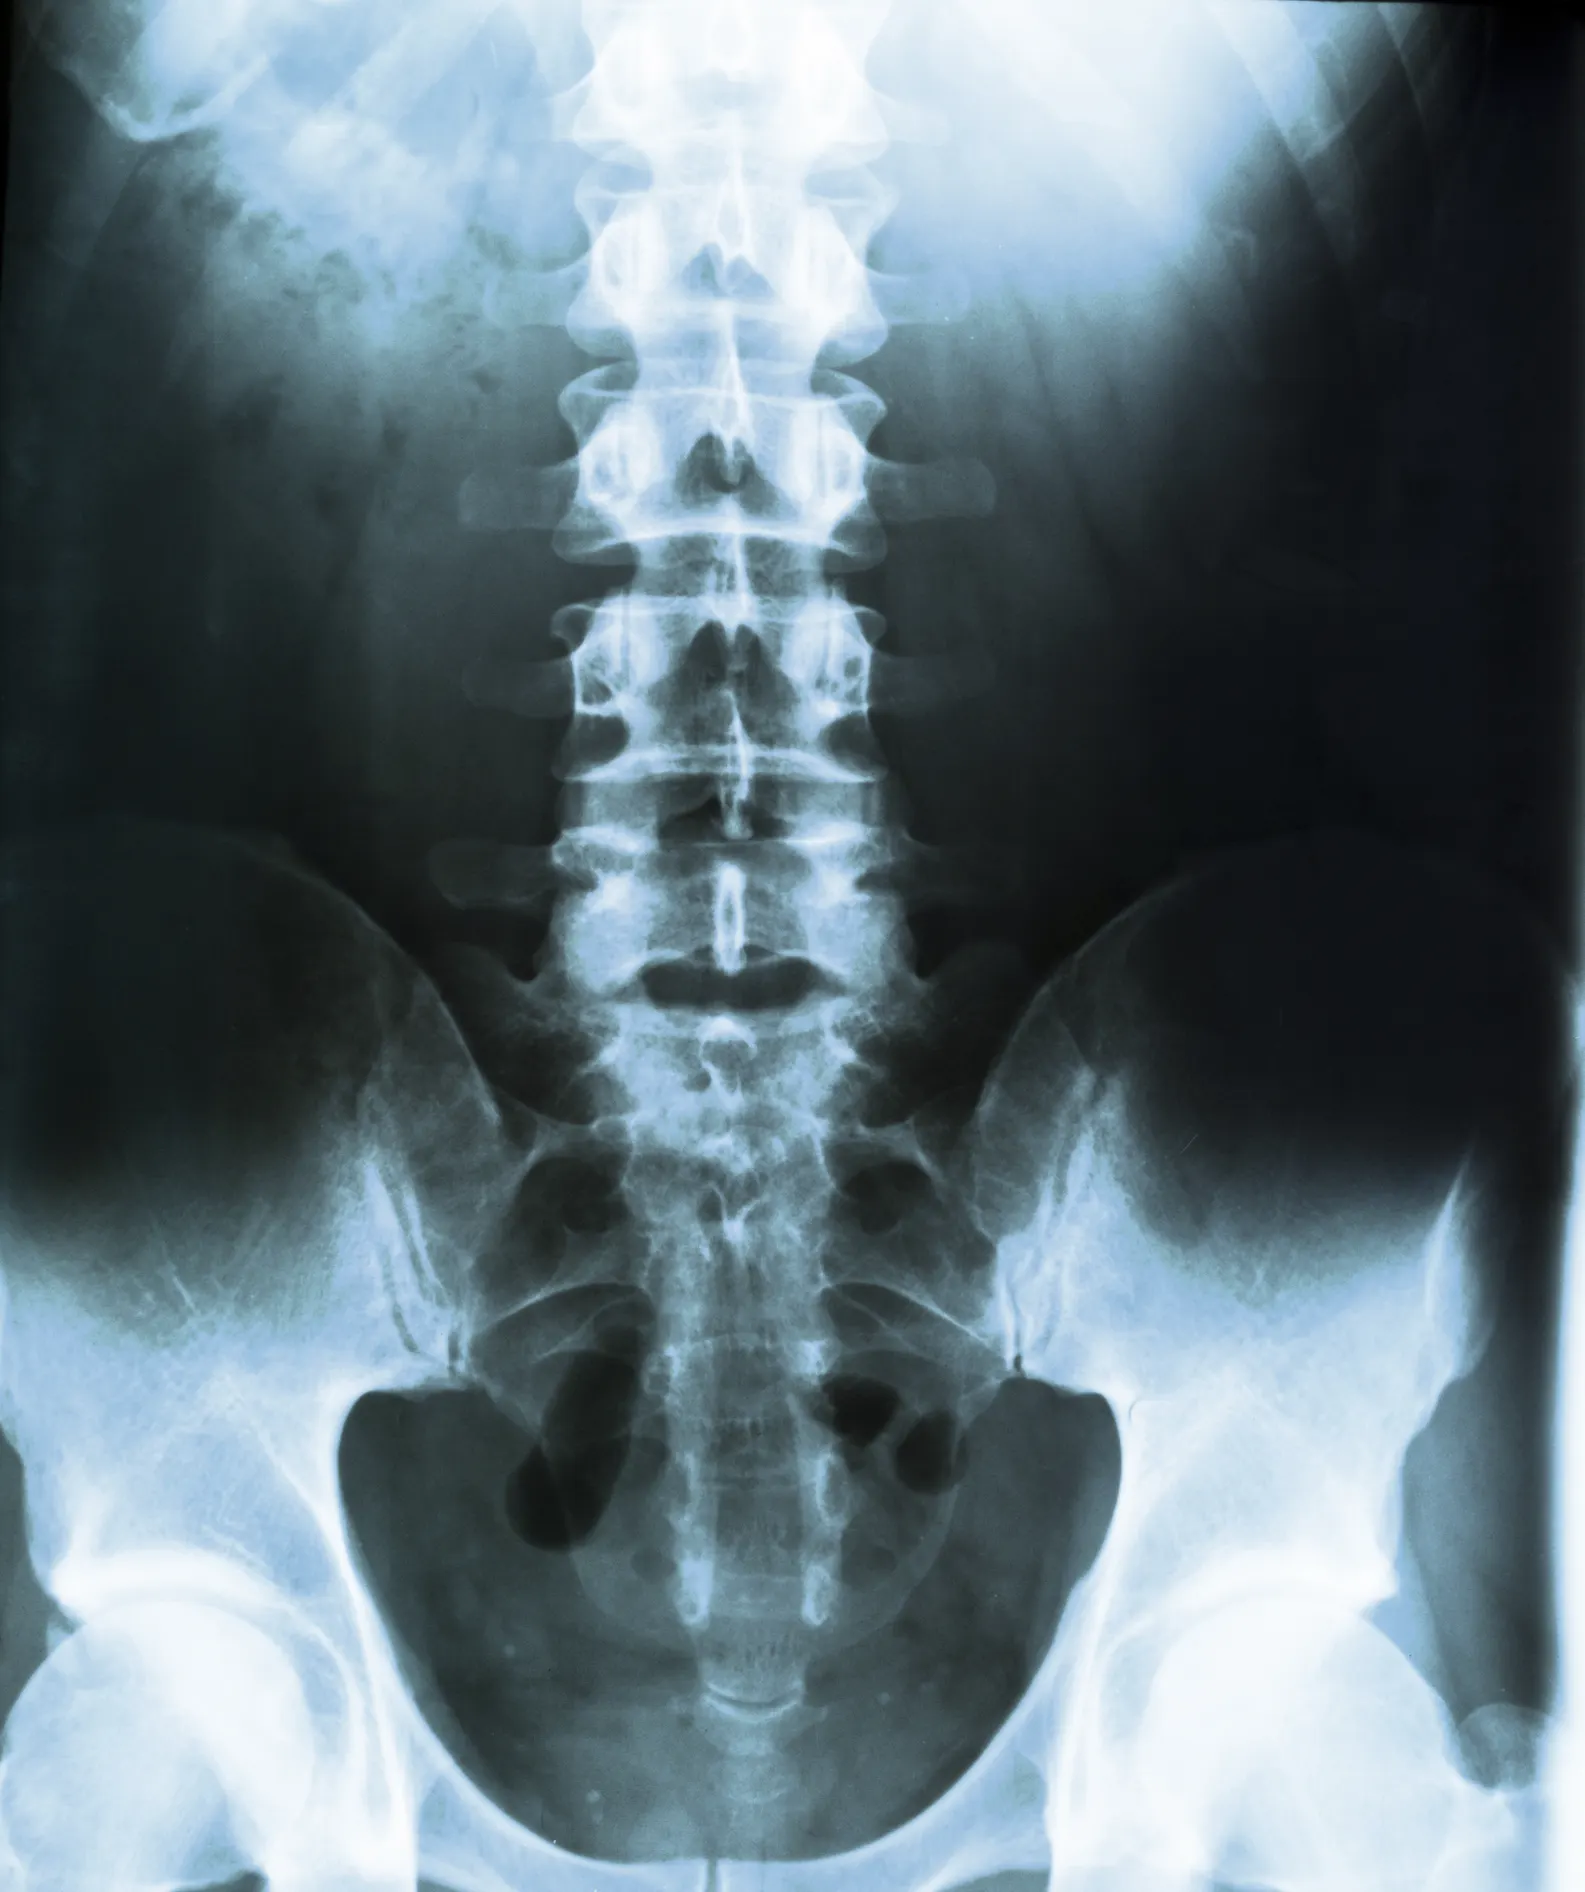

A conventional x-ray may be taken of the lower back (lumbar spine), upper back (thoracic spine), or neck (cervical spine) to confirm a suspected vertebral fracture. Additionally, vertebral imaging is used to identify any existing spinal fractures that are not causing symptoms.

A vertebral fracture assessment may be performed on the thoracic and lumbar spine at the same time as a bone mineral density test on a DEXA machine. This tool takes an x-ray image of the spine using lower radiation exposure than a standard x-ray.